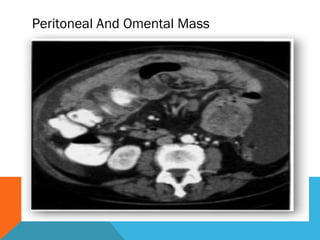

Mesentry And Omentum

 Infiltration and thickenining of mesentry

 Omental caking

 Nodular or strand like soft tissue density

 Calcified foci

 Rounded mass

Peritoneal And Omental Mass